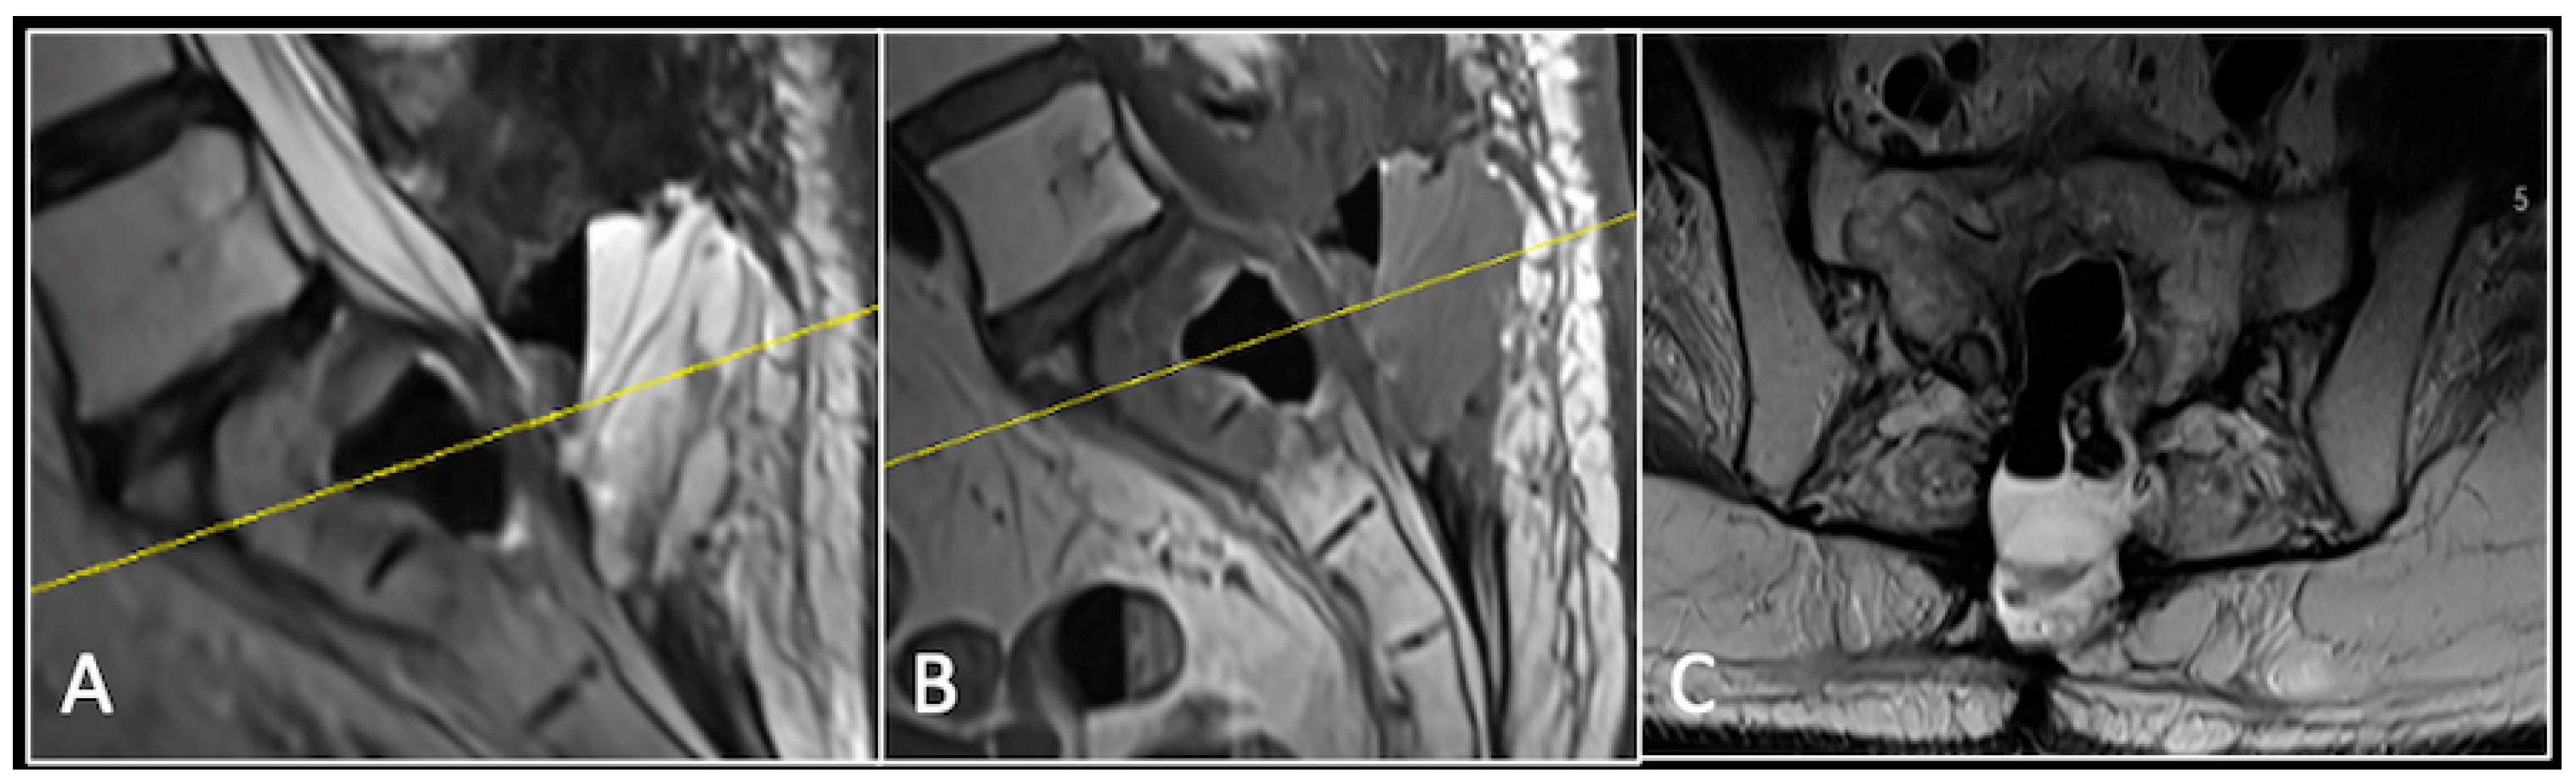

2.2. Case 2: Sacral Chordoma

This 63-year-old male presented with sacral pain and right-sided S1 radiculopathy. He was subsequently referred to our institution after diagnostic imaging revealed a destructive lesion within the S1 vertebra (Figure 4). The patient developed symptoms of acute cauda equina syndrome, for which we recommended an emergent surgical decompression to be performed at the referring hospital. Biopsy confirmed a conventional chordoma. The patient chose to undergo separation surgery, given the significant morbidity associated with an en-bloc sacral resection, including sacrifice of the neural structures innervating his bladder and bowel. He received adjuvant proton beam therapy, and 6-monthly surveillance imaging revealed stable disease (Figure 5). Unfortunately, 12 months post-separation surgery, there was evidence of tumour progression with epidural extension and symptomatic deterioration in bladder function, requiring revision surgical debulking (Figure 6).

Figure 4.

MRI demonstrating a destructive lobular sacral mass (arrow) with invasion of the S1 vertebral body and complete compression of the cauda equina neural elements. The yellow line on the axial image represents the plane of the corresponding axial section. (A) T2W sagittal; (B) T1W sagittal; (C) T2W axial.